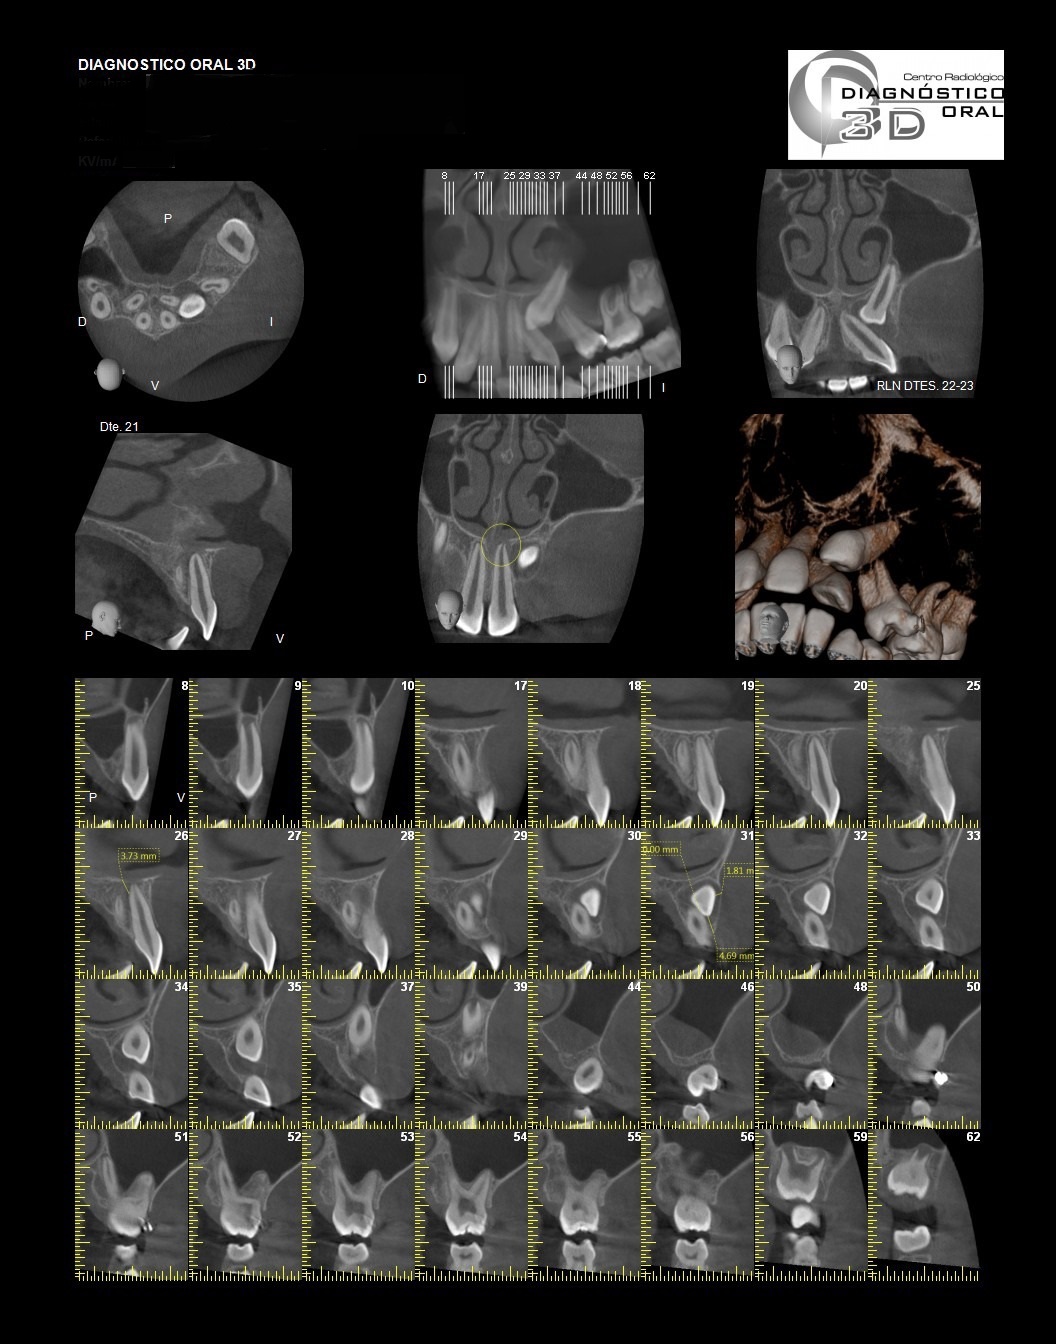

El Centro Radiológico Diagnóstico Oral 3D, es una empresa antioqueña que ofrece a sus pacientes desde el año 2009, tecnología de vanguardia en radiografías tridimensionales con calidad fotográfica. Las posibilidades para mejorar la eficacia en los diagnósticos bucales son evidentes, también lo son las posibilidades de manipulación de imagen. El sistema de imágenes en 3D ofrece detalles sin precedentes, convirtiéndola en la opción idónea para la mayoría de aplicaciones odontológicas, incluyendo implantes, tratamiento de conductos, ortodoncia, odontopediatría, periodoncia y cirugía

El mayor beneficiado con el uso de esta tecnología es el paciente, el cual podrá ser evaluado en todas sus dimensiones con una baja dosis de radiación, con un costo accesible y sin contaminar  el medio ambiente. Dependiendo de la necesidad del paciente, hay varios tipos de tomografías y los especialistas en el área odontológica hacen uso de ellas según su especialidad.

La radiología oral especializada es fundamental para una práctica dental integral, proporcionando información específica que influye en la toma de decisiones clínicas y mejora los resultados del tratamiento para los pacientes

Aplicaciones Clínicas:

Diagnóstico de caries y enfermedades periodontales

Evaluación de patologías dentales y maxilofaciales

Planificación de tratamientos ortodónticos y ortognáticos

Implantología dental

Diagnóstico de traumatismos dentales y maxilofaciales

Detección de lesiones quísticas y tumorales

Evaluación pre y postoperatoria de cirugías maxilofaciales